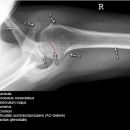

Scapula lateral (tangential, Leer-Larché)

Indikation

Impingementsyndrom und Rotatorenmanschettenläsion

Indikationen und Beurteilungskriterien

- Rotatorenmanschettenruptur (2,3): acromiohumerale Abstand <10 mm = Humeruskopf-Hochstand (< 10 mm verdächtig, < 6 mm beweisend). Knöcherne Vorsprünge am Schulterdach oder Oberarmkopf?, Methode der 1. Wahl = Sonographie

- Impingementsyndrom (2): Neigungswinkel des Acromions? Je gebogener bzw. hakenförmiger desto wahrscheinlicher ist ein Impingment, Zystenbildung im Bereich des Tuberculum majus, Subchondrale Sklerosierung des Tuberculum majus und subakromiale Osteophytenbildung (v.a. bei Beziehung zum Ursprung des Lig. acromioclaviculare), Sehnenverkalkungen (Supraspinatussehne)?

- bei Luxationen: Anteriore Luxation, Posteriore Luxation

- CAVE: Begleitverletzungen? (-> heute umfassend mit CT/MRT zu beurteilen)

- Hill- Sachs Läsion = Dorsokraniale Humeruskopf- Impressionsfraktur (50%) (Aufnahme der 1. Wahl: Stryker oder CT)

- umgekehrte Hill-Sachs Läsion = anteromediale Impression nach hinterer Luxation

- Bankart-Läsion: Abriss des vorderen Labrum-Kapsel-Komplexes bzw. Abrissfraktur des vorderen unteren Glenoidrandes (-> CT-Athrographie, Arthro-MRT)

- Tuberculum majus (15%), Pfannenrand